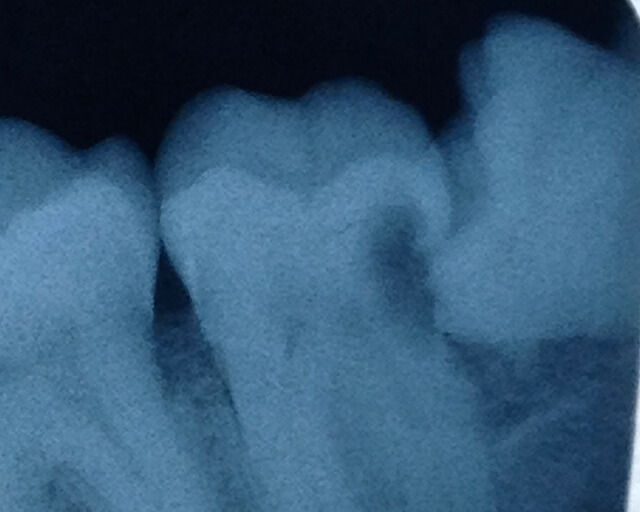

5. Is the tooth jammed against the next door tooth? We call it "impacted". If it is, then things get difficult.

Impacted wisdom toothIn the picture above, you can make out the wisdom tooth on the right side, tilted over and jammed up against the next door tooth. And it has caused a cavity in the side of the neighboring tooth. Both teeth will have to be removed.

When a wisdom tooth is jammed against the next one, it is automatically tilted and also in tight contact with that next tooth. So there is no room for the tooth to move. How on earth do we get that tooth out?